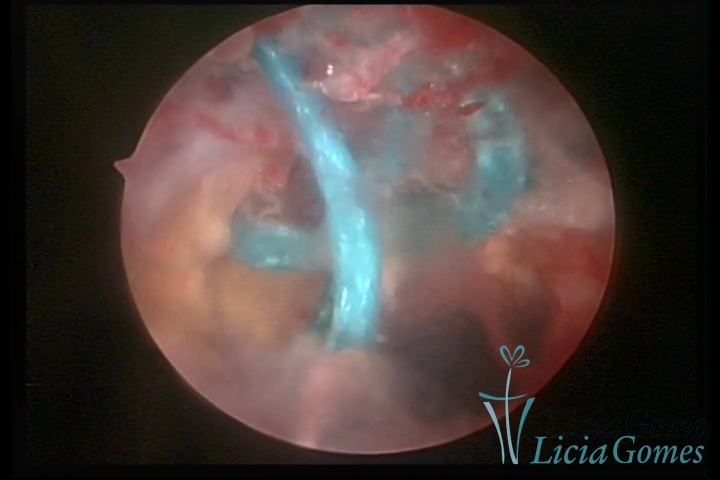

Cicatriz de cesárea com fio de sutura, não absorvido, como corpo estranho

×